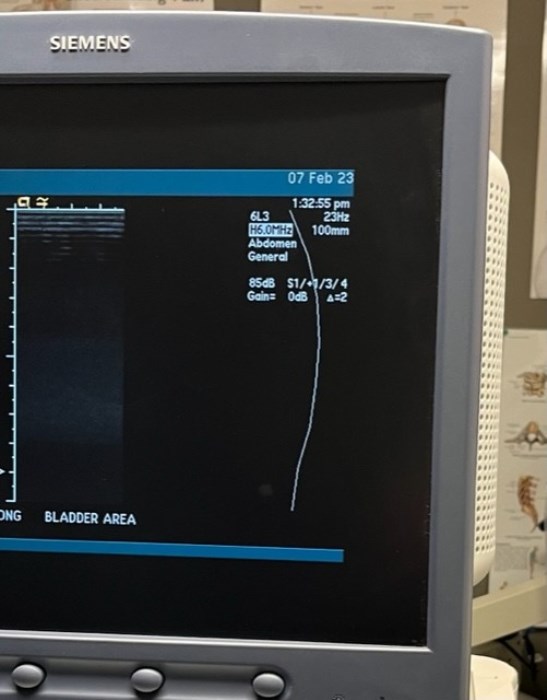

Siemens Sequioa Ultrasound

Pre-owned. In good working condition. Shown as is. Siemens Sequoia Ultrasound. DOM: 2006

Probes: 15L8w, 4V1, 10V4, 6L3, 4C1